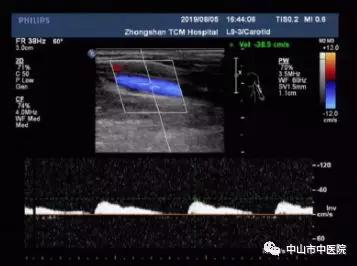

上举体位:桡动脉频谱血流低速低阻,收缩期时相延长